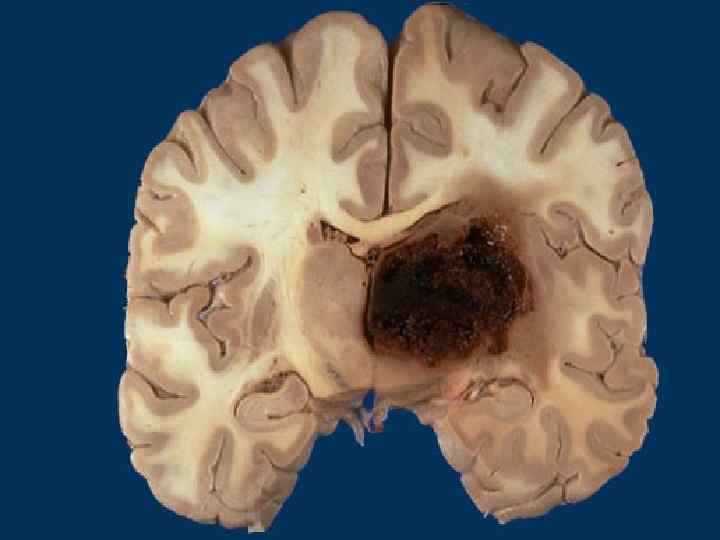

Морфология эклампсии Отек и кровоизлияния в головном мозге n «Токсическая дистрофия» печени n Некротический нефроз n Дистрофические и некротические изменения в органах n ДВС - синдром n